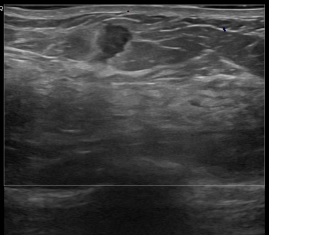

상기환자는 우측만져지는 멍울과 외부검사이상소견 내원하신 50대초반

여성분으로 의심스러운 우측혹 조직검사 시행해 유방암 진단되었습니다